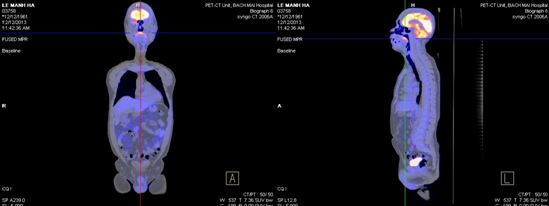

+ Tháng 12 năm 2013, bệnh nhân được chup PET/CT lần 2 sau khi kết thúc xạ trị và 4 đợt hoá trị. Trên hình ảnh PET/CT cho thấy: vùng đáy lưỡi có khối tăng hấp thu F-18 FDG, kích thước 3,9x4,3x3,0cm, theo dõi tổn thương viêm sau xạ trị. Không thấy hạch cổ tăng hấp thu F-18 FDG bất thường.

Hình 6. Hình ảnh PET/CT sau xạ trị 70Gy và 4 đợt hoá trị